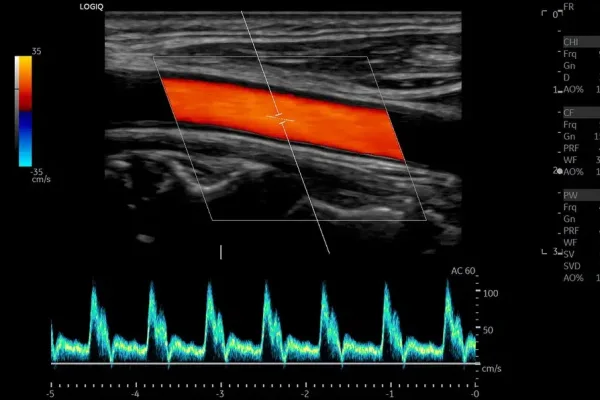

Échographie GE LOGIQ S8